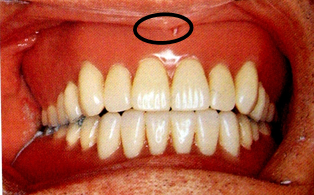

1.上唇系带(maxillary labial frenum)

上颌正中唇侧粘膜从牙龈交界处到上唇粘膜之间的粘膜皱襞,是口轮匝肌在上颌骨的附着处。

取印模时患者作唇的自主运动,并做肌功能修整,基托在此区应形成相应的切迹。